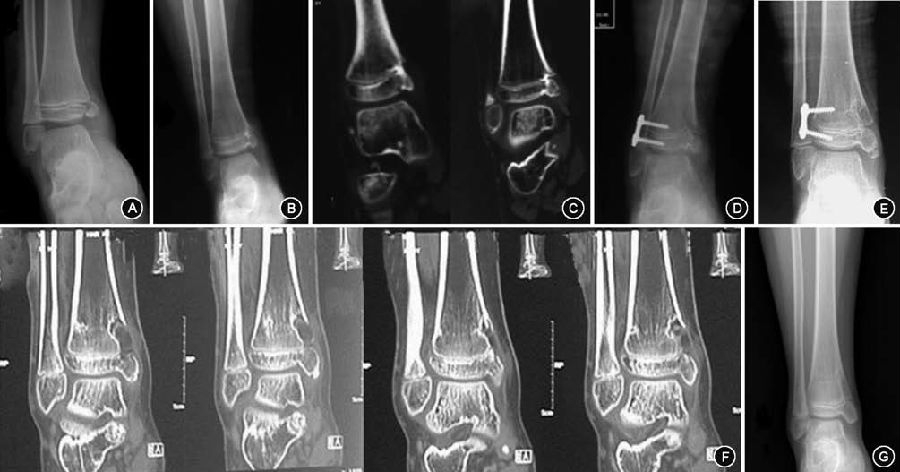

图3 7岁男性胫骨远端骺早闭,术前影像及术后随访 3A.外伤造成胫骨远端内侧骺损伤,原始损伤时的X线片;3B.伤后8个月出现踝内翻畸形,术前X线显示形成边缘型骨桥,内踝形态异常;3C.术前CT证实胫骨远端内侧存在骨桥; 3D.导航下行胫骨远端内侧骨桥切除,外侧“8”字钢板固定,手术后平片; 3E.术后10个月畸形矫正,骨桥消失,内踝形态基本正常;3F.取出“8”字钢板后行CT检查,证实骨桥已被空腔替代,同时空腔向干骺端生长证明局部具有生长潜力; 3G.术后16个月复查,踝关节形态基本正常